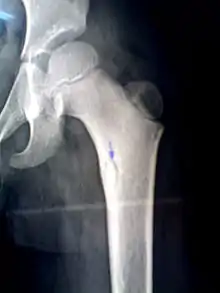

A sequestrum (plural: sequestra) is a piece of dead bone[1] that has become separated during the process of necrosis from normal or sound bone.

The sequestra are surrounded by sclerotic bone which is relatively avascular (without a blood supply). Within the bone itself, the haversian canals become blocked with scar tissue, and the bone becomes surrounded by thickened periosteum.

At the same time as this, new bone is forming (known as involucrum). Openings in this involucrum allow debris and exudates (including pus) to pass from the sequestrum via sinus tracts to the skin.